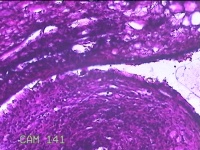

右侧卵巢囊肿及畸胎瘤

性别

女

年龄

23岁

临床诊断

右侧卵巢囊肿破裂 右侧卵巢畸胎瘤

一般病史

下腹痛30分钟。

标本名称

大体所见

灰白暗红色囊性肿物4.5x3x0.8cm一个,表面糜烂,因已切开,内容物已流失,内见大量油脂,囊壁厚约0.1cm。

这个片子没法诊断。